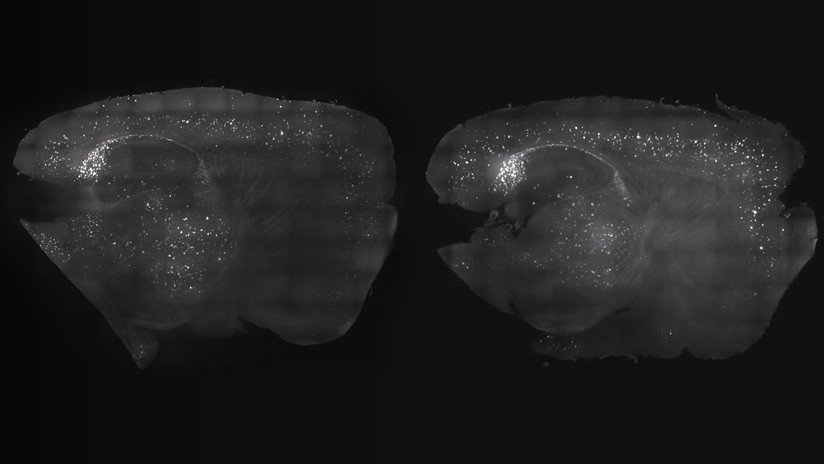

Descubrieron que, a pesar de que la intensidad de la neurogénesis disminuye con la longevidad, el proceso no concluye totalmente ni aun en la edad senil. Así, los científicos detectaron neuronas emergentes en el hipocampo de una persona de 87 años.

En contrapartida, sí se registró una reducción drástica en la aparición de nuevas neuronas en humanos que sufrían de alzhéimer, lo que abre nuevas perspectivas para el tratamientos de las enfermedades del espectro demencial.

"La detección precoz de una disminución en la generación de nuevas neuronas podría ser un marcador temprano de la enfermedad", cita Efe a Llorens Martín.